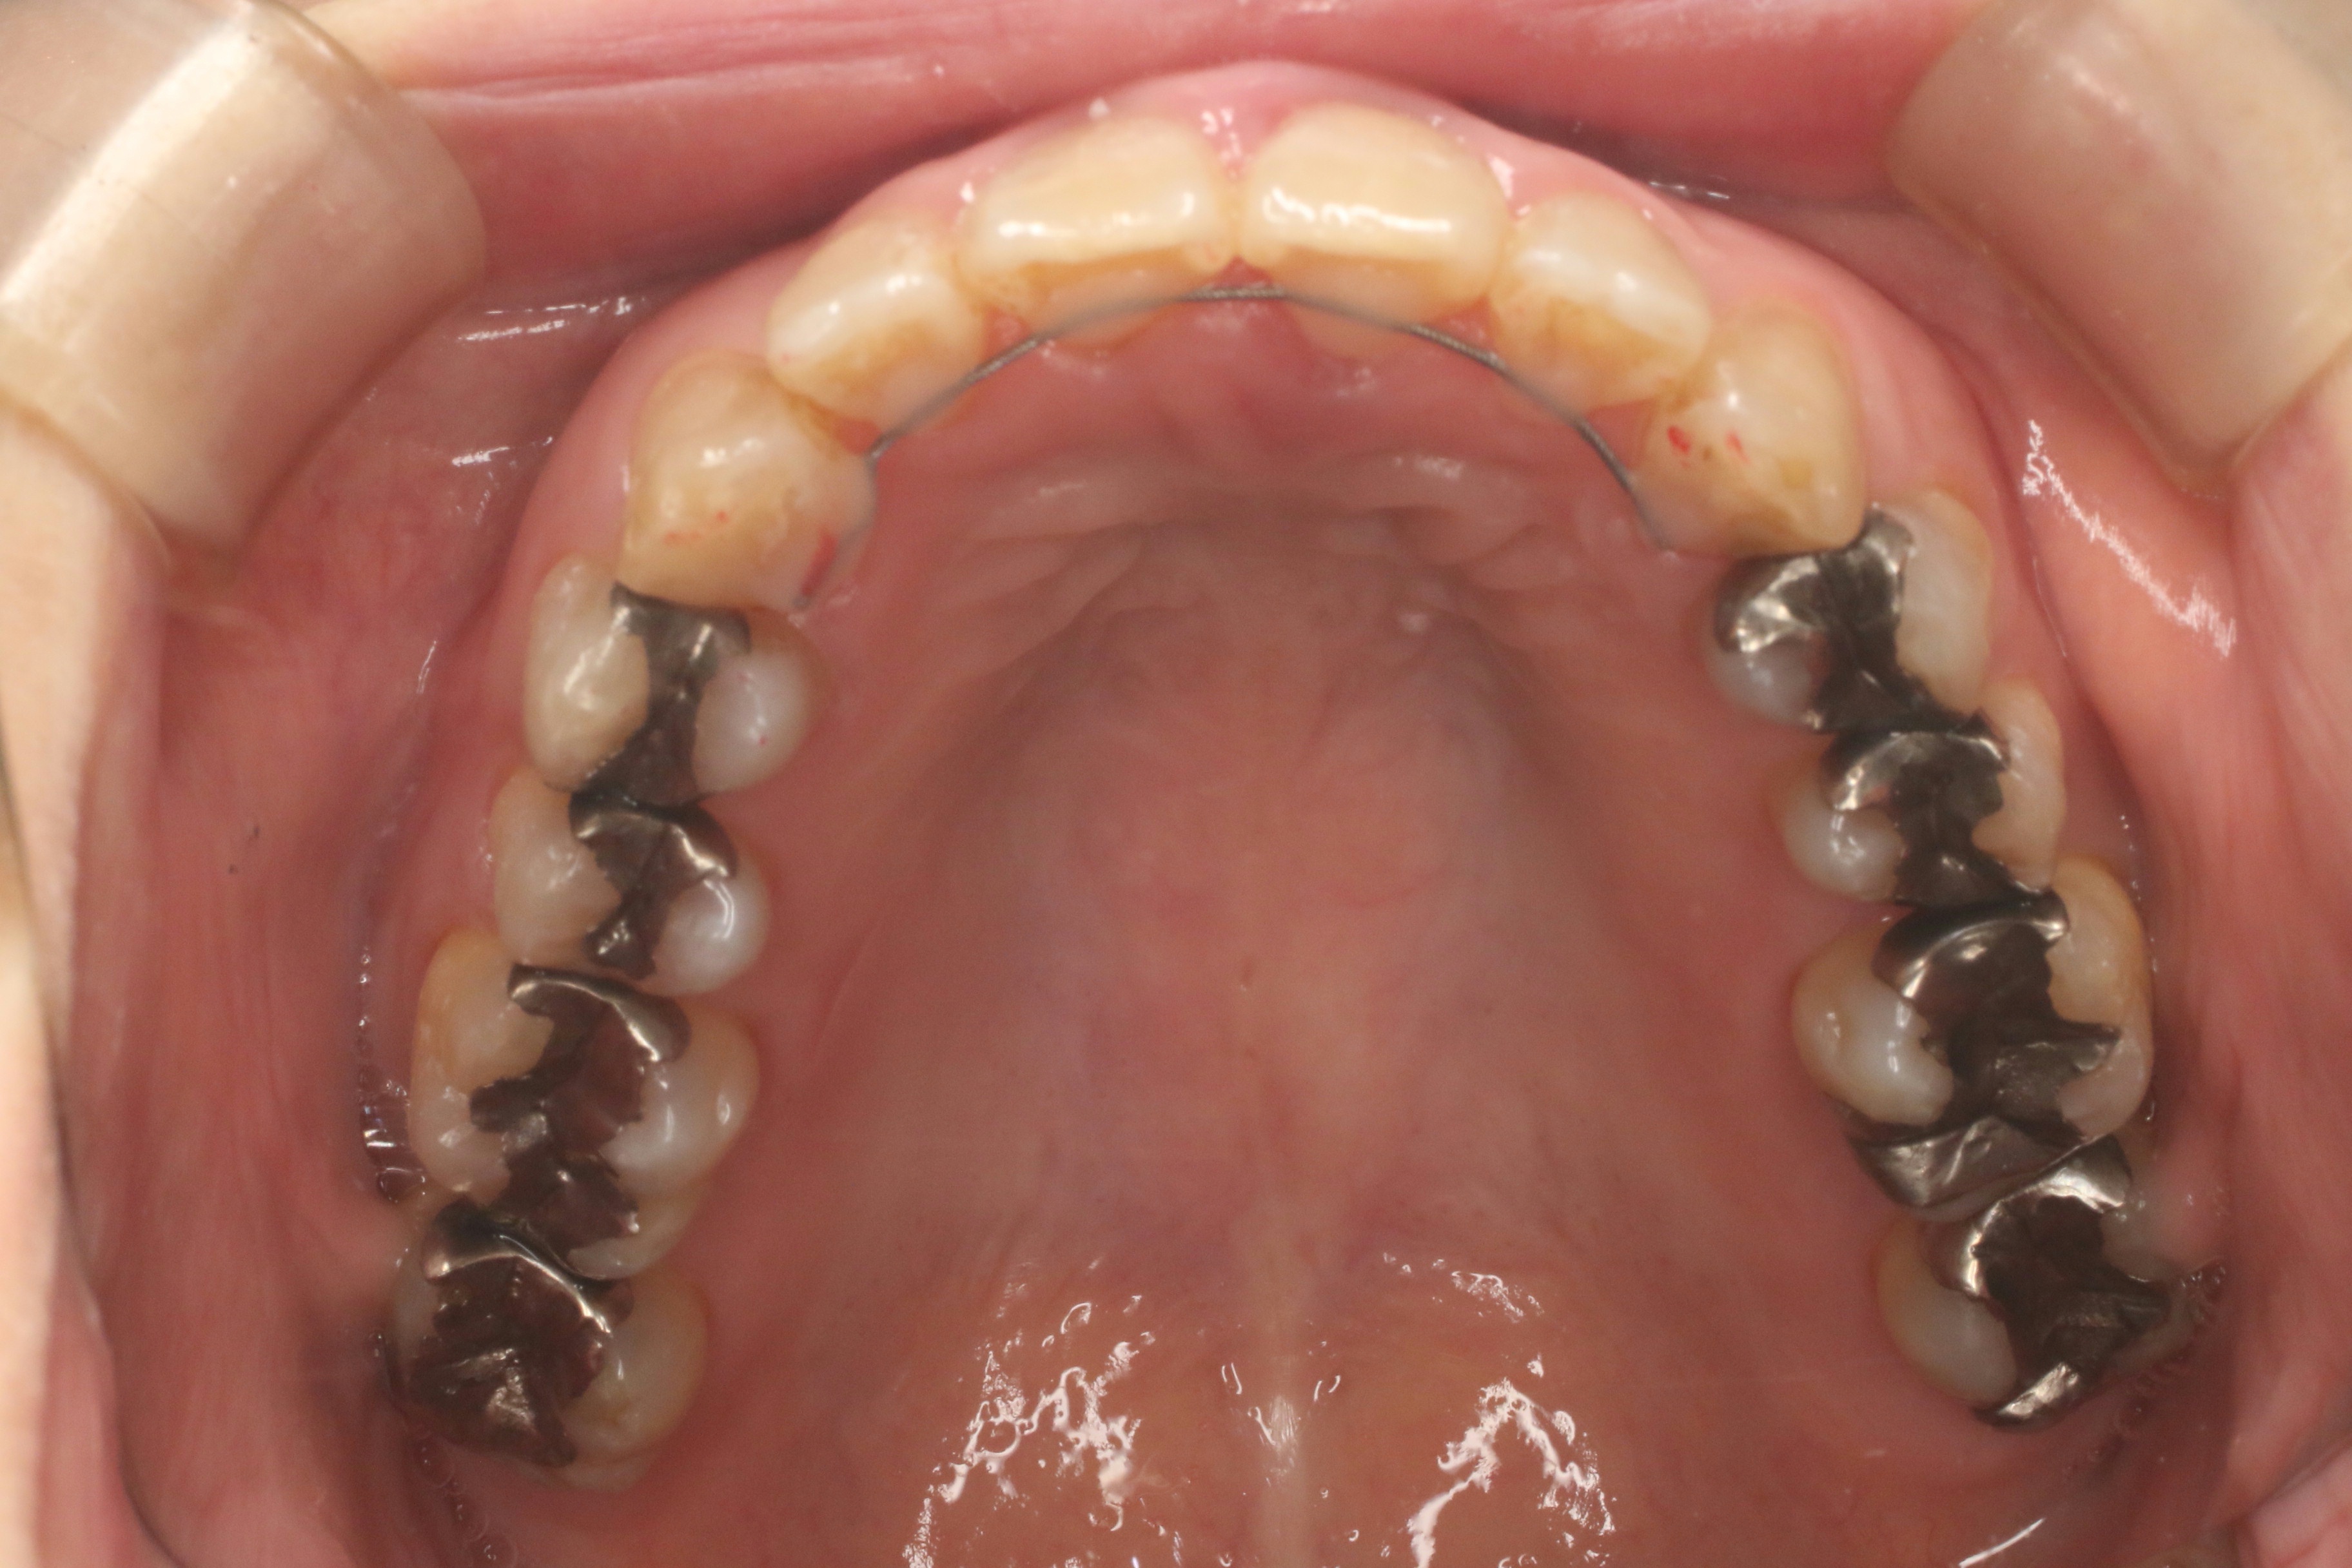

すきっぱ(治療期間:1年/通院回数12回)

年齢層

50代

性別

女性

主訴

すきっぱ

治療費用

1,177,000円

治療期間

1年

抜歯

非抜歯

矯正の装置

ラビアル

副作用、リスク

・知覚過敏・痛み・発音障害・体質により金属アレルギーの発症・歯肉退縮・歯根吸収・ブラックトライアングル(歯と歯の間の根元にできる隙間)・歯磨きが上手く出来ない場合、むし歯や歯周病が進行・保定が不十分の場合、後戻りの可能性

Before

After